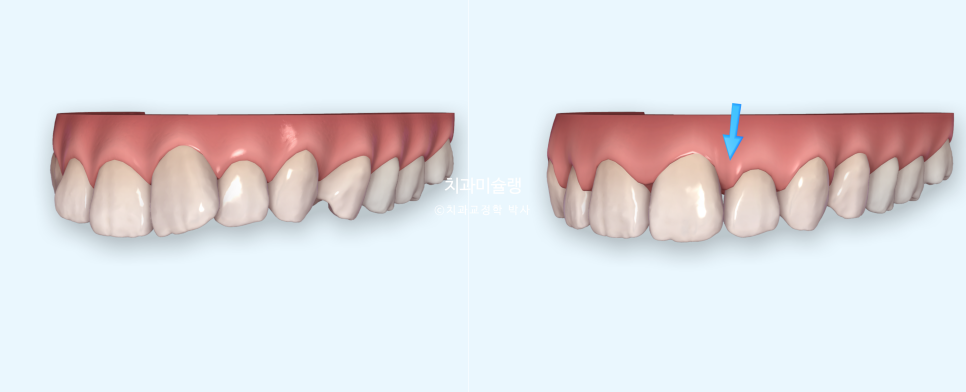

자, 이제 블랙트라이앵글이 어느부위에 어느정도 사이즈로 생길지 시각화해서 확인했으니

해결방법을 설명할 시간입니다.

치간삭제로 블랙트라이앵글이 줄어드는 과정도 교정상담 첫날 미리 확인할 수 있습니다.

사진은 위에서부터 차례대로

초진

단순 배열 후 블랙트라이앵글의 발생

소량의 치간삭제로 블랙트라이앵글 사이즈가 줄어든 모습 입니다.

치면당 0.2mm를 한계로 설정해놓고 치간삭제를 시행하면 치아가 약해지거나 시릴 가능성은 없습니다.